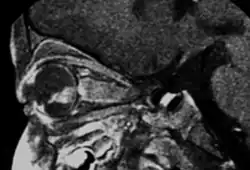

-

Drawing of a large retinoblastoma -

Aspect of trilateral retinoblastoma on MRI -

An ocular ultrasound of a large retinoblastoma tumor within the eye of a 3-year-old boy -